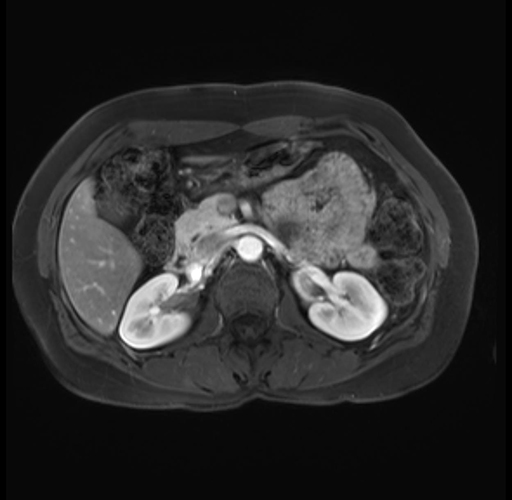

Imaging Analysis

Look through the patient's CT scan to identify any areas of concern for the necessary procedure.

Based on your CT findings, which issue(s) are present and would give reason for "planned slowing down moment(s)" in this case?